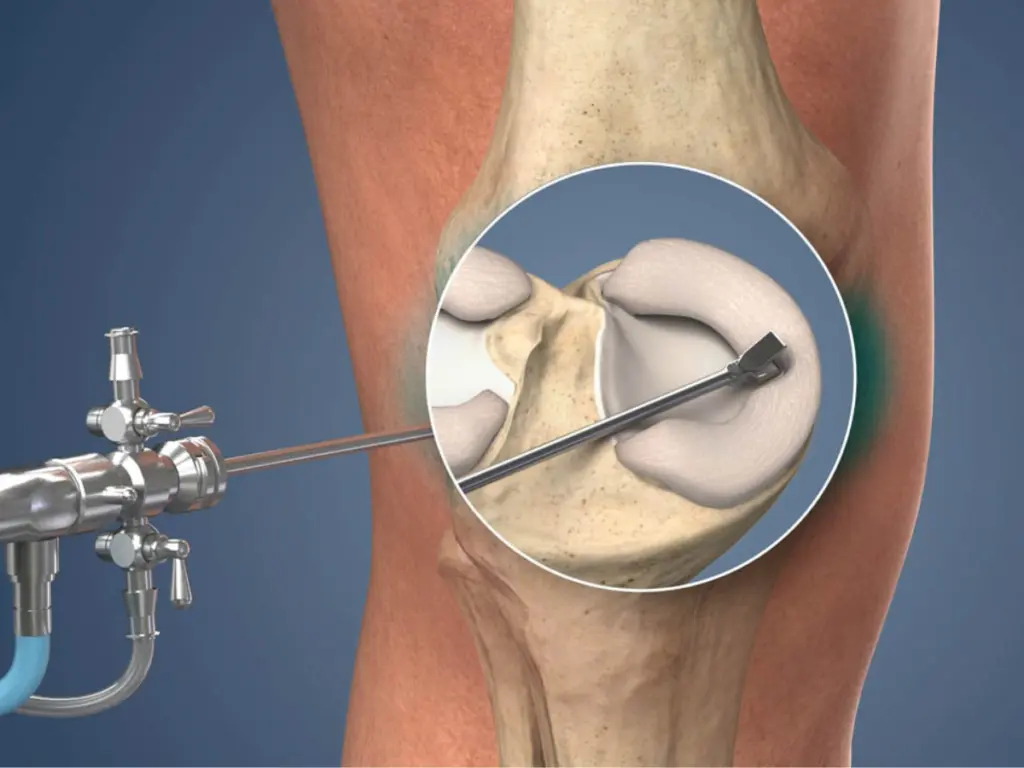

Revision knee replacement involves removing the old or problematic implant and replacing it with a new, highly stable prosthesis. This procedure is more detailed and technically demanding than primary knee replacement and requires an experienced surgeon skilled in managing infection, implant loosening, misalignment, and bone loss.

Revision knee surgery requires specialized implants, advanced surgical planning, and expert execution. Dr. Akash Saraogi uses the latest global techniques including computer-assisted alignment, bone reconstruction, revision-grade implants, and minimally invasive approaches when suitable.

✔ Precise implant removal